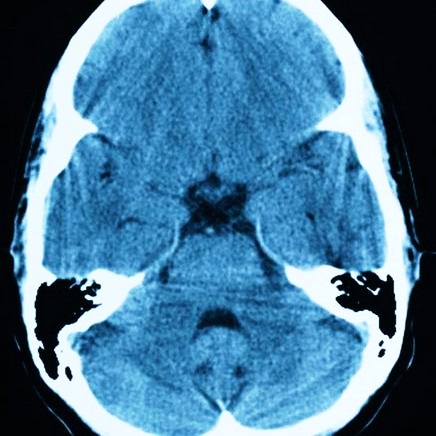

- арахноидальная. Она может локализоваться как на поверхности, так и в слоях оболочки. Кистозная капсула наполнена ликвором. Чаще всего ее диагностируют у представителей сильной половины человечества в разном возрасте, обычно это киста височной доли. Когда значение внутреннего давления в опухоли превышает показатель давления внутри черепной коробки, она начинает давить на мозговую кору. При увеличении подобных новообразований в размере может появиться тошнота вплоть до рвоты, судороги и галлюцинации. Когда внутреннее содержимое начинает увеличиваться в объеме, у пациента может воспалиться мозговая оболочка. Эта патология требует обязательного обращения в медучреждение, так как при апоплексии кисты может наступить смерть;

- церебральная киста. Она формируется не на поверхности, а во внутренних слоях головного мозга из-за смерти клеток мозга. Чтобы остановить омертвение мозга, следует своевременно установить причину отмирания этих клеток. Вызвать развитие такой опухоли могут и новые инфекционные очаги, трепанация черепа, слабое снабжение кровью мозга, а также микроинсульты. Если такое новообразование продолжает расти в диаметре, назначается операция;

Без адекватного лечение кистозное образование в мозгу опасно развитием эпилептических припадков, а у больных с кистой в районе ствола может развиваться дизартрия и дисфагия. Если не обращать внимания на кисту промежуточного паруса, дело может закончиться гидроцефалией, синдромом сдавливания структур мозга или кровоизлиянием. Но самым страшным последствием для любого пациента с кистой в мозгу является внезапная смерть.